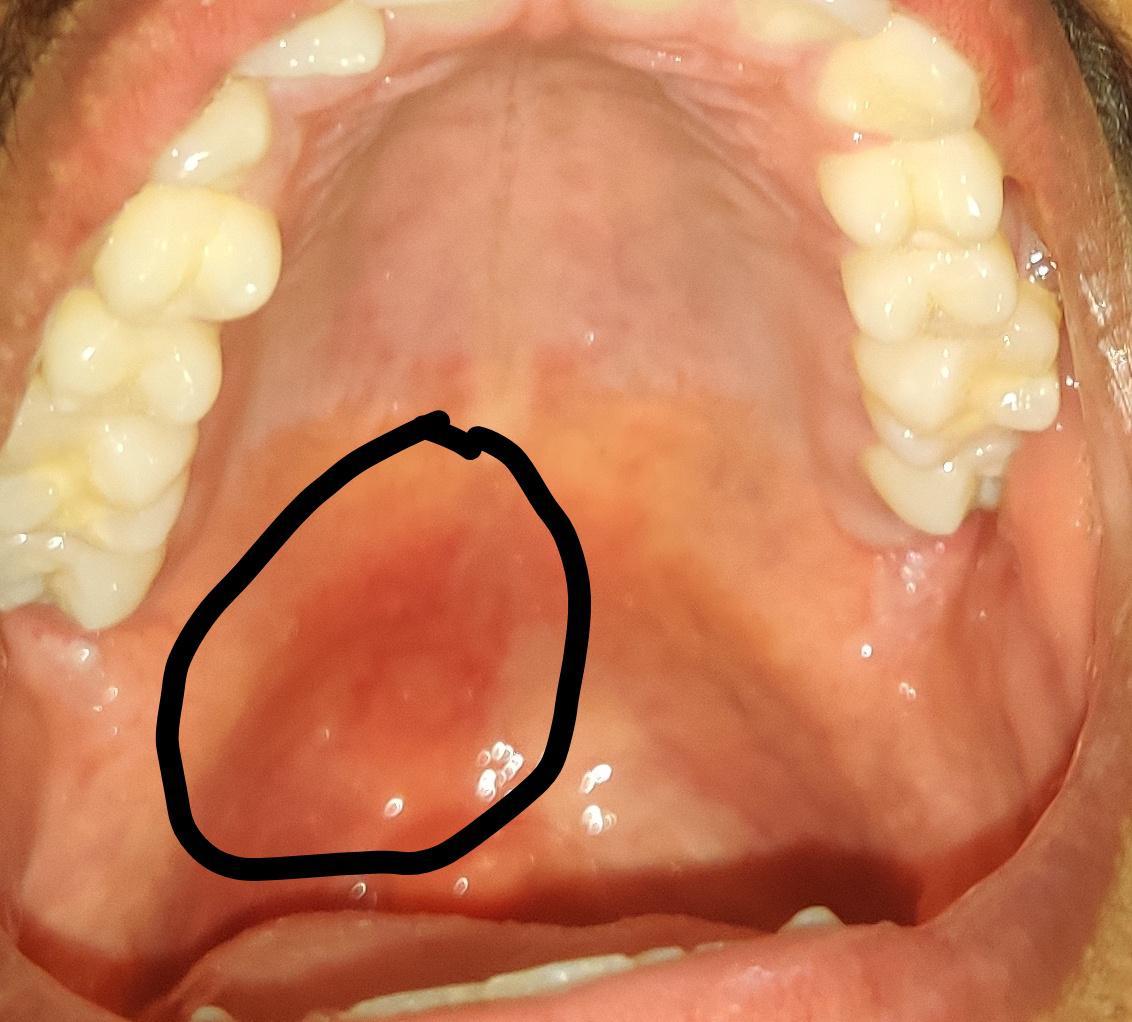

What Is Palate Bruise . Injuries to the palate are relatively common in the pediatric population. However, if you experience severe pain,. Palatal petechiae refer to pinpoint, round, red, or purple spots found on the soft palate (the part of the roof of your mouth located towards the back). Having a bruise on your palate can be a painful and uncomfortable experience. If the roof of your mouth (palate) is sore, it can make eating and drinking uncomfortable and difficult. Petechiae is bleeding in the skin caused by broken blood vessels. Palatal petechiae is a bruised palate, or the roof of your mouth. A palate bruise can be a surprising and uncomfortable issue, affecting the roof of one’s mouth. The palate, or roof of the mouth, is a delicate area. This condition typically heals on. These spots arise from small. A child’s propensity to place objects in their mouth, along with their unsteady gait, make trauma to. In most cases, a bruised roof of the mouth will heal on its own within a week or two. You may also have problems speaking normally.

What Is Palate Bruise Palatal petechiae is a bruised palate, or the roof of your mouth. This condition typically heals on. You may also have problems speaking normally. The palate, or roof of the mouth, is a delicate area. Having a bruise on your palate can be a painful and uncomfortable experience. These spots arise from small. If the roof of your mouth (palate) is sore, it can make eating and drinking uncomfortable and difficult. However, if you experience severe pain,. Injuries to the palate are relatively common in the pediatric population. Palatal petechiae refer to pinpoint, round, red, or purple spots found on the soft palate (the part of the roof of your mouth located towards the back). In most cases, a bruised roof of the mouth will heal on its own within a week or two. A palate bruise can be a surprising and uncomfortable issue, affecting the roof of one’s mouth. Palatal petechiae is a bruised palate, or the roof of your mouth. Petechiae is bleeding in the skin caused by broken blood vessels. A child’s propensity to place objects in their mouth, along with their unsteady gait, make trauma to.